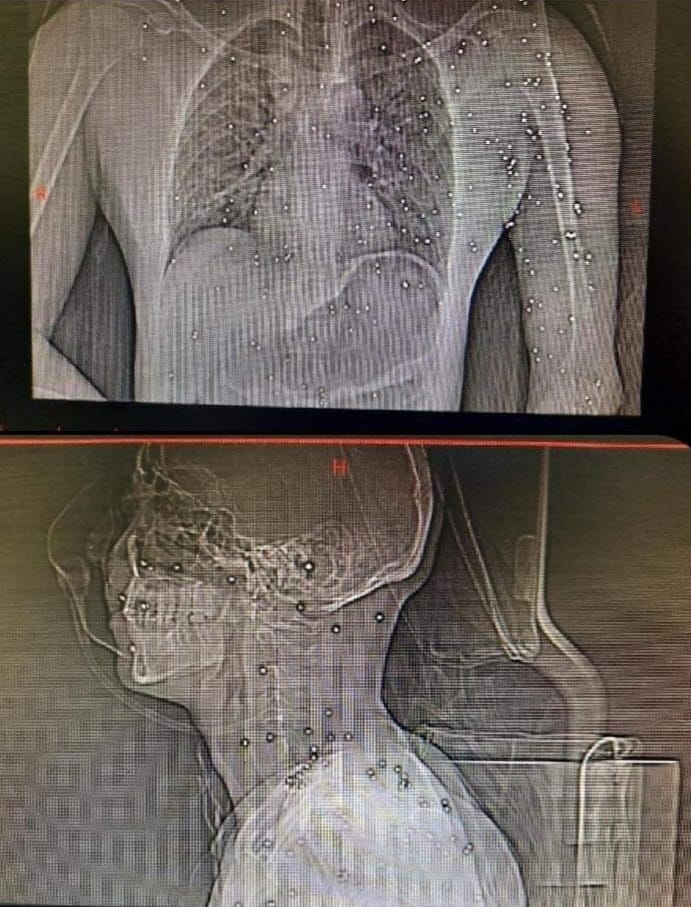

These X-ray images provided to @CBSNews by health care workers in #Iran appear to show a protester's head and torso riddled with lead shotgun pellets. Image

The wounded have been hit by a variety of weapons, from "plastic to lead pellets to Kalashnikovs, even sniper fire," the Iranian doctor said, adding that he has helped some of the injured in their homes, despite the risk of getting arrested for doing so.

He says he receives photos like this ... "So, a person who is bleeding out of their leg from like, a gunshot wound, is just waiting for my response on the phone. ... It's just a horrible situation." Image

@DrKayvanMirhadi tries to connect them with trusted doctors on the ground in Iran, but failing that, he attempts to guide them through home remedies. His message for #Iranian authorities: "At least let the doctors treat them. Don't take the ambulances to detention centers." Image